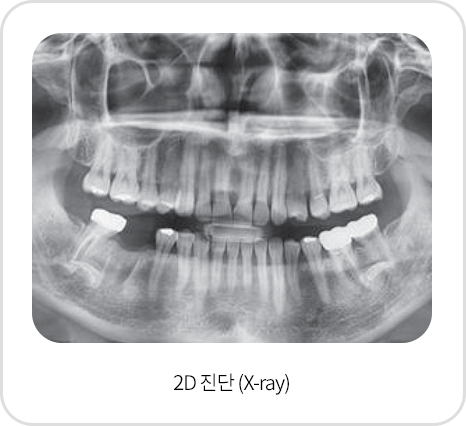

01

스마트한 디지털 방식 진단

3D CT촬영으로 x-ray및 육안 진단만으로는 보이지 않는 뼈 조직의 상태,

신경의 위치까지 3차원 정밀 진단이 가능하여 보다 안전한 임플란트 수술로 성공률이 높습니다.